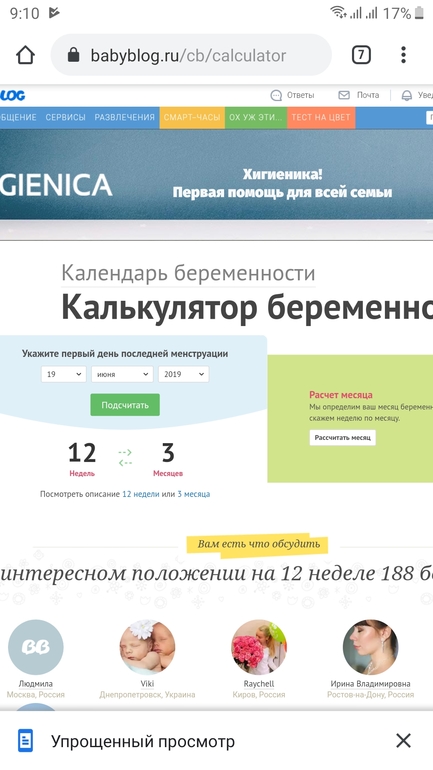

Всем привет, сегодня 12 недель по подсчетам календаря. Последние месячные 19 июня. Пришла на узи, врач сказала что еще слишком рано что по узи где то 9.5 недель. И трижды спросила про миому, небыло ли у меня ее. Я вся в растроеных чувствах, сказала прийти через 2 недели. Что может быть? Я спросила все ли впорядке? Она сказала что сердцебиение есть ручки и ножки вижу и пока что все. Вот такой скрининг, несостоявшийся. Дело в том что у меня четкий менструальный календарь все четко как в швейцарском банке, беременность не планировали но так уж вышло, у кого нибудь так было что срок по узи меньше?спасибо всем неравнодушным.

Как у вас может быть 12 недель? У меня последние месячные были 18 июня и сегодня у меня 11 недель и 1 день.

Ну как бред, цикл мой 28 дней, 19 июня месячные начались, 5 дней. 23 закончились. Прибавляем 10 дней овуляция с 2го, я веду менструальный календарь несколько лет. На бебиблоге не нормальный календарь? А нормальный это какой?

Да ладно, странно просто. Я тоже веду много лет календарик. И просто посчитала с первого дня последних М и так по неделькам до сегодня. У меня ровные недельки по вторникам. Последние М были 18.06. Цикл 26 дней. М шли 5 дней. Овуляцию по тестам отслеживала. С 1 июля был 1ДПО. Три календарика скачены и все показывают 12-я неделька.

У меня тоже монстры последние были 19.06 но срок 10,6 дней, а по узи вчера поставили 11,2! На скрининг только 11.09 записалась! Я думаю вы со сроками запутались!